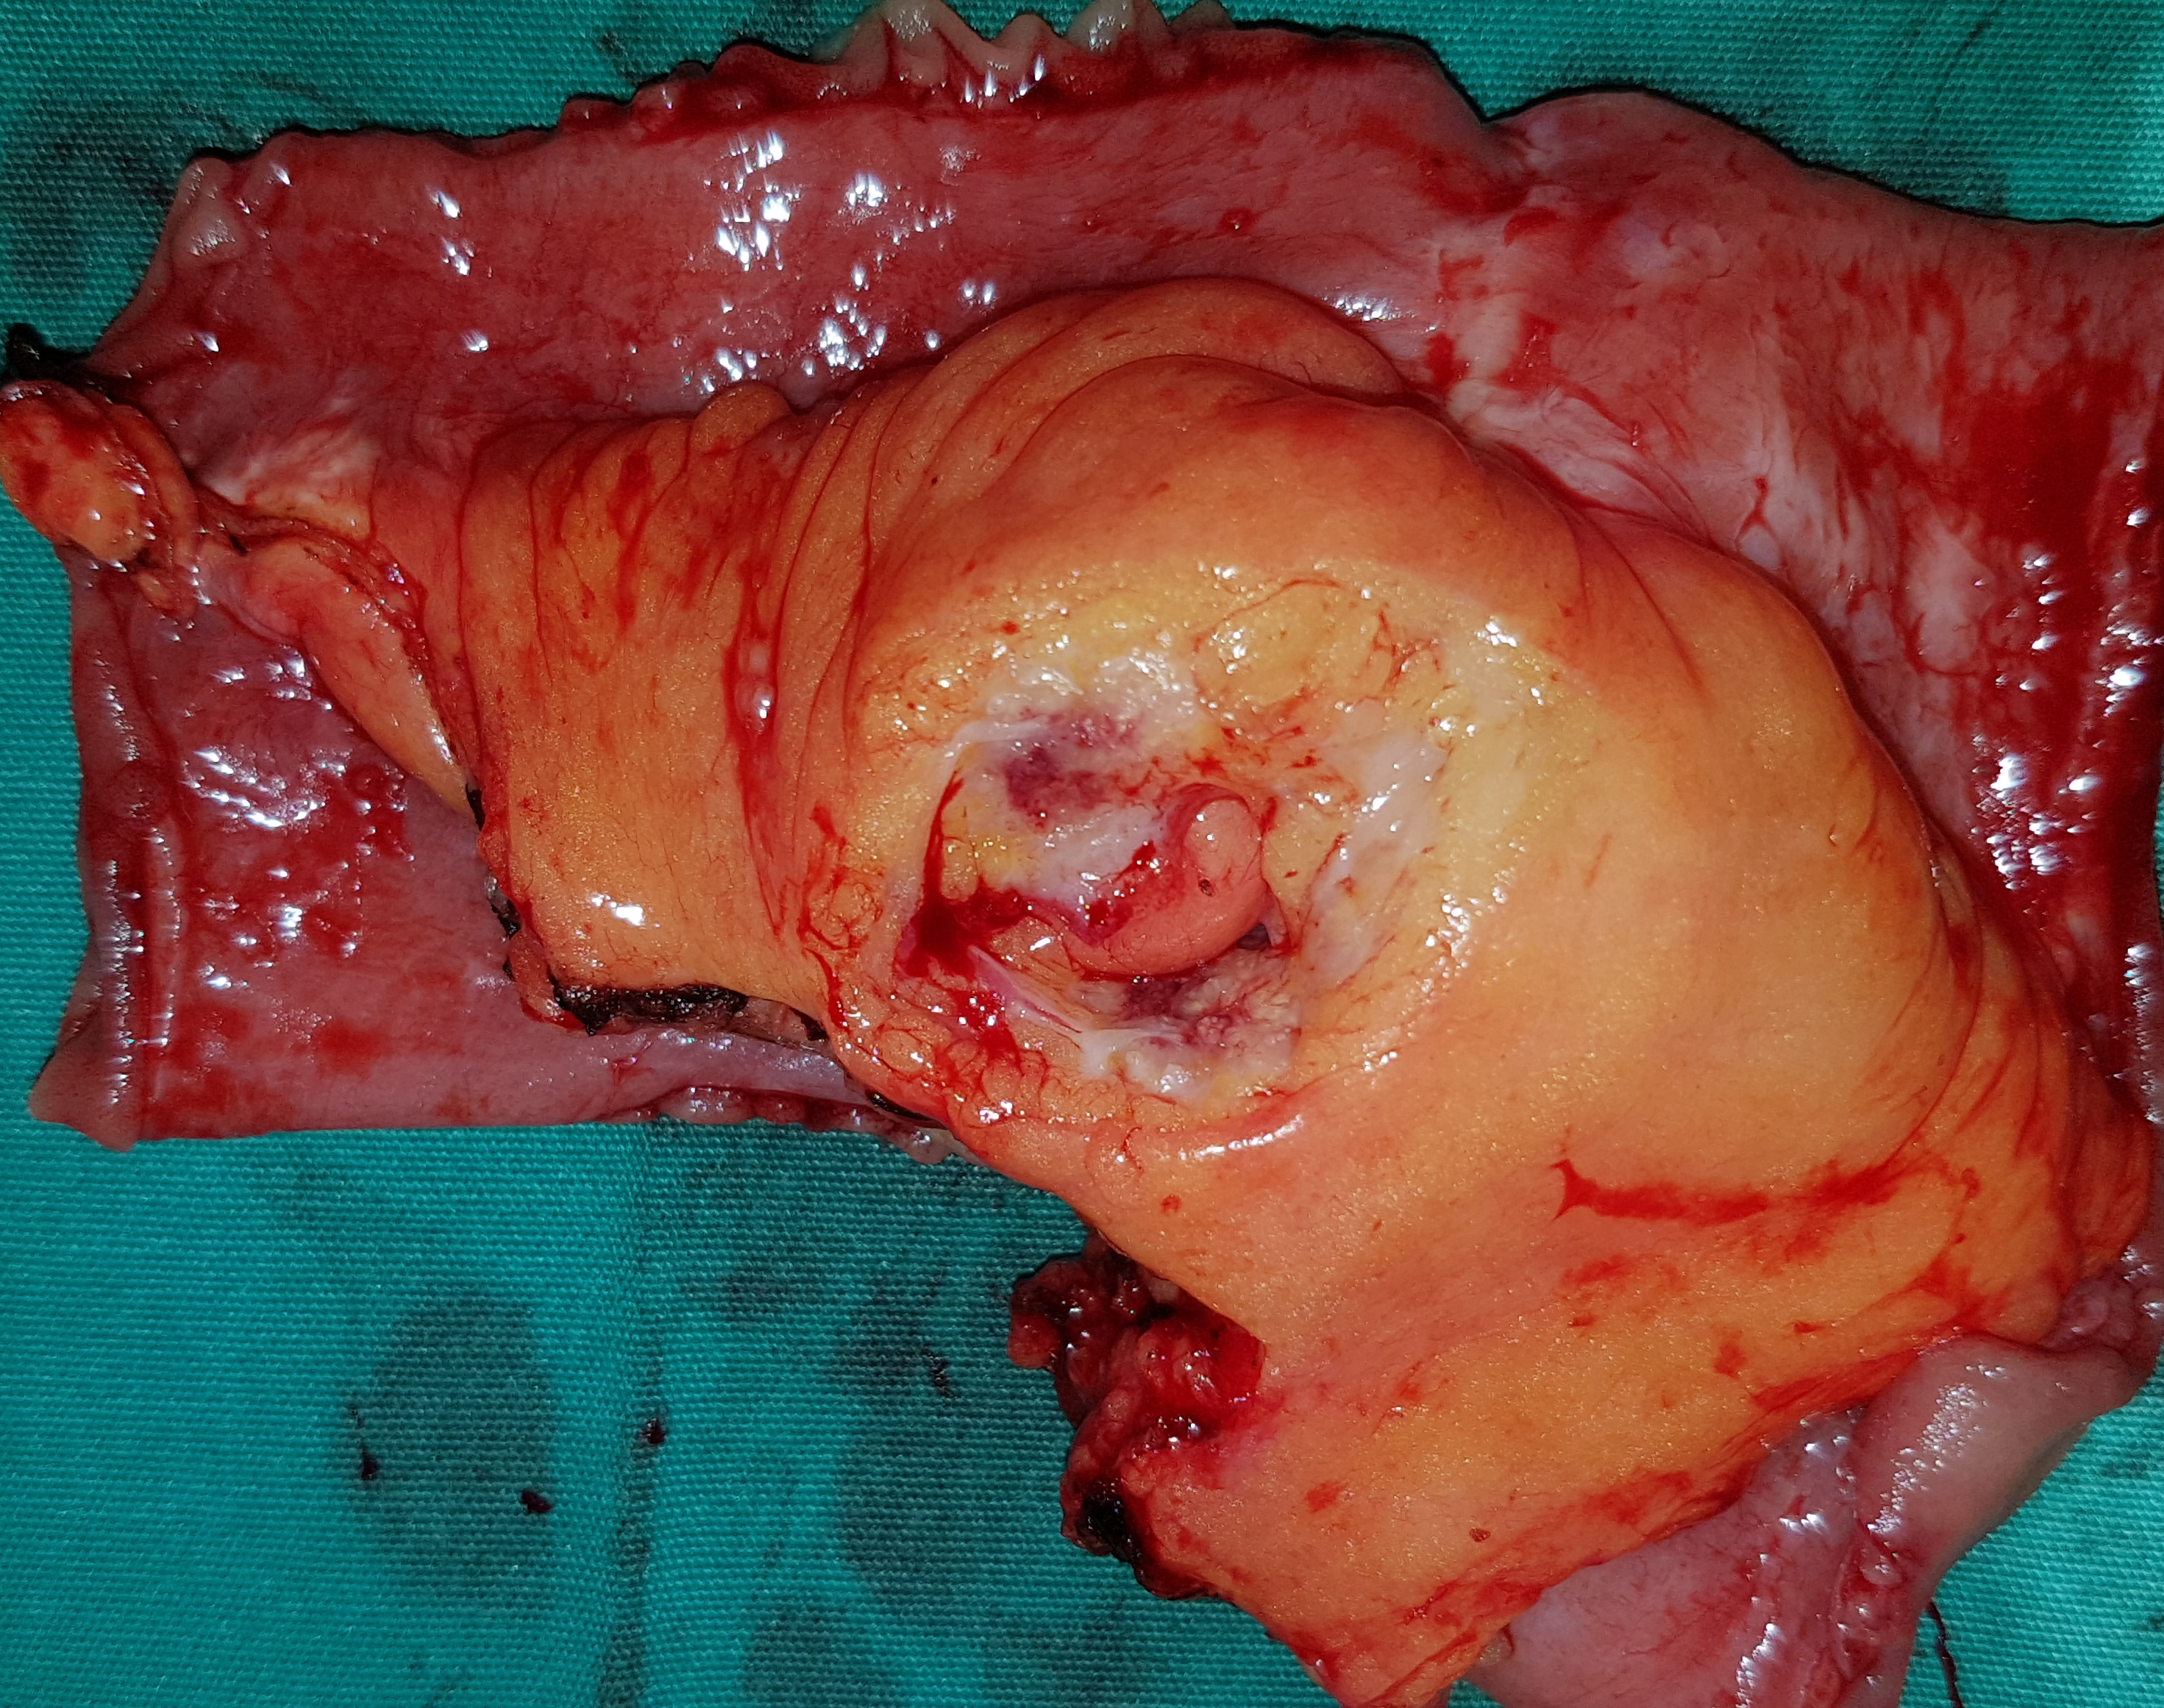

Μακροσκοπική εμφάνιση ωοθήκης μετά ολική υστερεκτομή σε γυναίκα 46 ετών με μετάχρονες ωοθηκικές μεταστάσεις που διαγνώστηκαν δύο χρόνια μετά δεξιά ημικολεκτομή για καρκίνωμα ανιόντος κόλου. Η μακροσκοπική εμφάνιση του ωοθηκικού όγκου αναδεικνύει κυστικές και στερεές περιοχές (Ευγενική παραχώρηση Dr. V. Penopoulos)